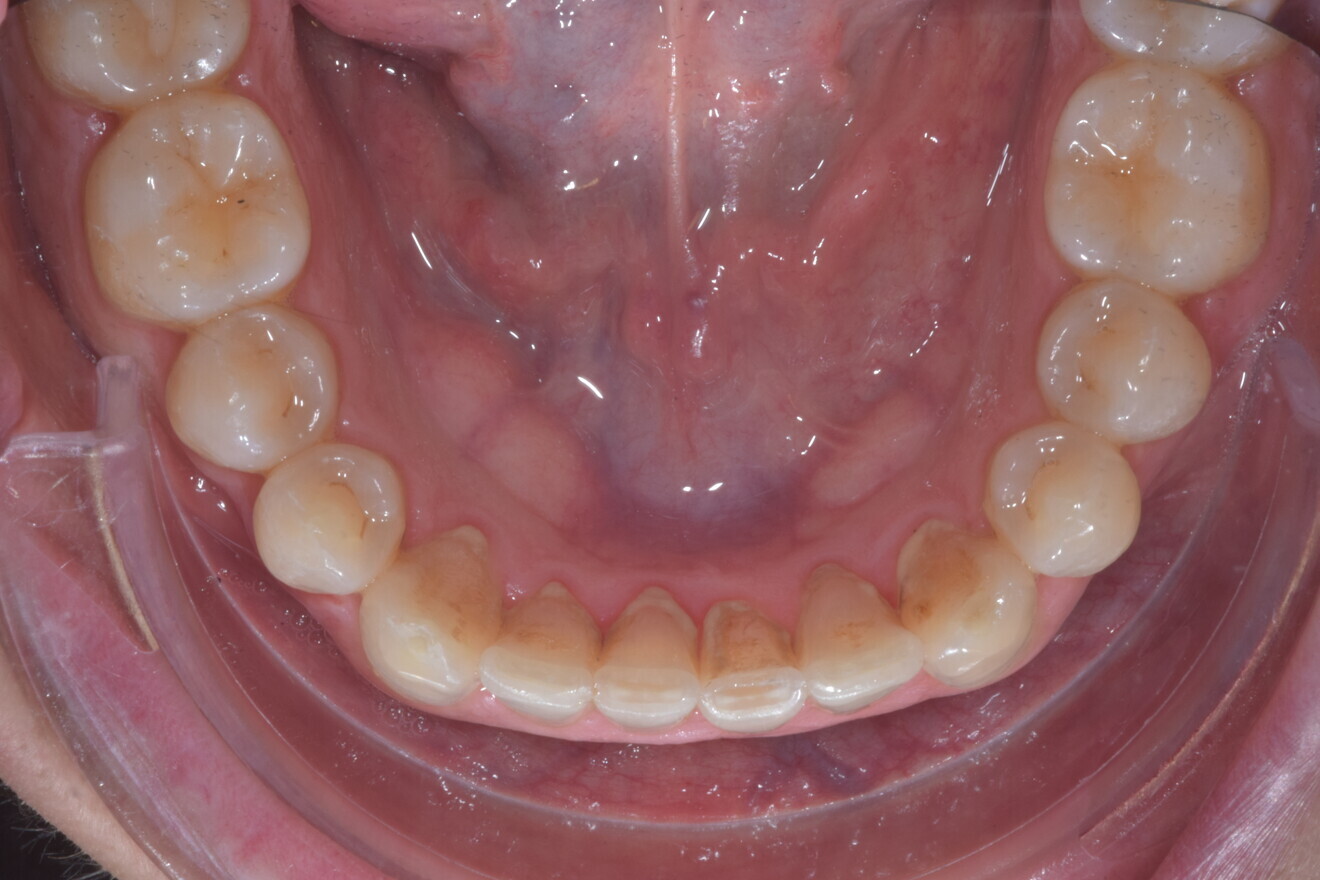

The digital treatment plan (ClinCheck) provided 12 aligners for the maxillary arch and 17 for the mandibular arch. The treatment objectives were focused on coupled vertical movements of posterior extrusion and anterior intrusion by means of bite ramps, providing for posterior disocclusion and anterior intrusion of mandibular teeth by means of extrusion attachments needed for mandibular arch levelling. The maxillary and mandibular incisors were proclined to level the upper and lower curve of Spee and to support the flat profile and the lips. Class II elastics were planned to support mandibular proclination and heavy posterior occlusal contacts with relative posterior extrusion. Lateral and posterior maxillary torque were planned to be close to 0°, to achieve wider arch design and ideal intercuspation. No digital over-engineering was planned in the set-up. Because of the age of the patient, the aligners were changed every ten days for a treatment time of less than six months. At the end of the first stage of aligners (Figs. 20–24), an additional stage was planned to improve molar intercuspation without elastics with a digital plan of five further aligners. This brought the total treatment time to 7.5 months since the additional aligners were changed every week.

At the end of the treatment, Class I canine and molar relationships were obtained, maxillary incisor inclination was slightly increased (Ui–FH = 112°), mandibular incisor inclination (IMPA = 97.09°) was fully corrected by means of proclination and the divergency was slightly increased (SN–GoGn = 27°) because of the relative posterior extrusion and use of Class II elastics—a small variation (1°), which is interesting considering the age of the patient (Figs. 25–35). A balanced smile arc was obtained with an ideal relationship between the maxillary incisors and lower lip, and torque control of the lateral and posterior segments generated a broader smile.

At the one-year follow-up in retention (Vivera retainers with bite ramps, Align Technology), the result was stable and intercuspation was improved (Figs. 38–42).